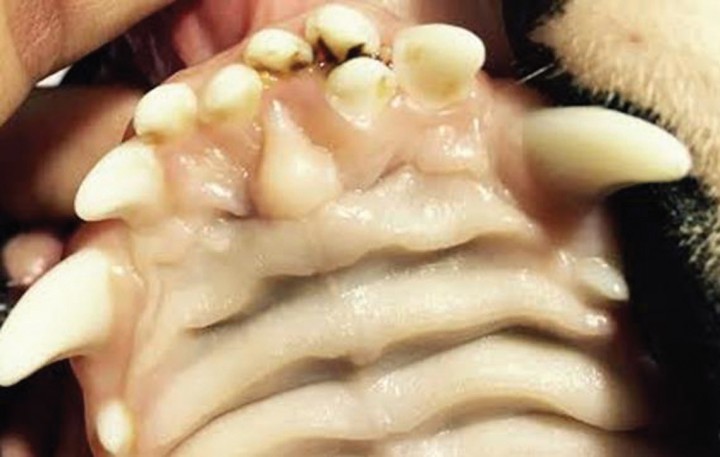

Quiste dentígero /quiste folicular

Se trata de una estructura quística que se origina de forma secundaria a un diente no erupcionado (impactado o incluido).[ Brook AN. Pathology in the pediatric patient. En: Niemiec B: Small Animal Dental, Oral and Maxillofacial Disease. Manson Publishing. London 2010; 90-123. , Wiggs RB, Lobprise HB. Veterinary Dentistry, Principles and Practice. Lippincott-Raven, Philadelphia. 1997; 130; 440-444; 472-474 . , Neville BW, Damm DD, Allen CM, Bouquot JE. Oral and Maxillofacial Pathology. WB Saunders, Philadelphia. 2002. ]

El esmalte se forma y desarrolla antes de la erupción dentaria por el órgano formador de esmalte o folículo, integrado en unas células llamadas ameloblastos.[ Brook AN. Pathology in the pediatric patient. En: Niemiec B: Small Animal Dental, Oral and Maxillofacial Disease. Manson Publishing. London 2010; 90-123. , Whyte A, Whyte J, Sopena J, et al. Atlas de Odontología en pequeños animales. Edimsa. Madrid 1998; 42. ] Si el diente erupciona de manera convencional, el órgano formador de esmalte se desgasta rápidamente. Si por el contrario un diente no erupciona, los ameloblastos persisten y forman una estructura en forma de saco revestida de epitelio.[ Brook AN. Pathology in the pediatric patient. En: Niemiec B: Small Animal Dental, Oral and Maxillofacial Disease. Manson Publishing. London 2010; 90-123. , Wiggs RB, Lobprise HB. Veterinary Dentistry, Principles and Practice. Lippincott-Raven, Philadelphia. 1997; 130; 440-444; 472-474 . ] Este epitelio puede ser, o no, productivo. En la mayor parte de los casos produce líquido y dará lugar a una formación quística.[ Brook AN. Pathology in the pediatric patient. En: Niemiec B: Small Animal Dental, Oral and Maxillofacial Disease. Manson Publishing. London 2010; 90-123. , Neville BW, Damm DD, Allen CM, Bouquot JE. Oral and Maxillofacial Pathology. WB Saunders, Philadelphia. 2002. ] Es importante resaltar que no todos los dientes no erupcionados desarrollarán quistes.[ Brook AN. Pathology in the pediatric patient. En: Niemiec B: Small Animal Dental, Oral and Maxillofacial Disease. Manson Publishing. London 2010; 90-123. ]

Estas estructuras se pueden presentar en la dentadura de leche, pero son más comunes en la permanente. Cuando su tamaño es reducido, generalmente son asintomáticos, pudiendo apreciarse áreas de inflamación en zonas desprovistas de dientes.[ Brook AN. Pathology in the pediatric patient. En: Niemiec B: Small Animal Dental, Oral and Maxillofacial Disease. Manson Publishing. London 2010; 90-123. ] Si por el contrario el quiste alcanza gran tamaño, puede originar una pérdida ósea significativa o destrucción de tejidos adyacentes en función de la presión ejercida.[ Brook AN. Pathology in the pediatric patient. En: Niemiec B: Small Animal Dental, Oral and Maxillofacial Disease. Manson Publishing. London 2010; 90-123. , Wiggs RB, Lobprise HB. Veterinary Dentistry, Principles and Practice. Lippincott-Raven, Philadelphia. 1997; 130; 440-444; 472-474 . , Neville BW, Damm DD, Allen CM, Bouquot JE. Oral and Maxillofacial Pathology. WB Saunders, Philadelphia. 2002. ] En ambos casos pueden producirse infecciones[ Brook AN. Pathology in the pediatric patient. En: Niemiec B: Small Animal Dental, Oral and Maxillofacial Disease. Manson Publishing. London 2010; 90-123. , Neville BW, Damm DD, Allen CM, Bouquot JE. Oral and Maxillofacial Pathology. WB Saunders, Philadelphia. 2002. ] (a veces son confundidos con abscesos) y neoplasias como el ameloblastoma[ Brook AN. Pathology in the pediatric patient. En: Niemiec B: Small Animal Dental, Oral and Maxillofacial Disease. Manson Publishing. London 2010; 90-123. , Neville BW, Damm DD, Allen CM, Bouquot JE. Oral and Maxillofacial Pathology. WB Saunders, Philadelphia. 2002. , Kramek BA, O’Brien TD, Smith FO. Diagnosis and removal of a dentygerous cyst complicated byan ameloblastic fibro-odontoma in a dog. J Vet Dentistry 1996, 13(1):9-11. [PMC] , Castelló P, Borrego J, Ortega J. Clasificación, diagnóstico y tratamiento de los tumores odontogénicos. Clín Vet Peq Anim 2014; (34) 4:194-200. ] y carcinoma de células escamosas.[ Brook AN. Pathology in the pediatric patient. En: Niemiec B: Small Animal Dental, Oral and Maxillofacial Disease. Manson Publishing. London 2010; 90-123. , Neville BW, Damm DD, Allen CM, Bouquot JE. Oral and Maxillofacial Pathology. WB Saunders, Philadelphia. 2002. ]

El diagnóstico se realiza mediante radiología[ Brook AN. Pathology in the pediatric patient. En: Niemiec B: Small Animal Dental, Oral and Maxillofacial Disease. Manson Publishing. London 2010; 90-123. , Neville BW, Damm DD, Allen CM, Bouquot JE. Oral and Maxillofacial Pathology. WB Saunders, Philadelphia. 2002. ] (se debe radiografiar cualquier zona de ausencia dental). Revelan un área radiolúcida asociada a la corona de un diente no erupcionado (Fig. 10). El diagnóstico definitivo es a través de anatomía patológica.[ Brook AN. Pathology in the pediatric patient. En: Niemiec B: Small Animal Dental, Oral and Maxillofacial Disease. Manson Publishing. London 2010; 90-123. ]

<p>A. Se observa la ausencia del canino inferior derecho (404). El segundo premolar inferior derecho (406) no ha erupcionado completamente. B. Radiografia lateral oblicua de la mandíbula. Se aprecia la presencia de un quiste dentígero secundario a un diente no erupcionado (impactado o incluido).</p>

A. Se observa la ausencia del canino inferior derecho (404). El segundo premolar inferior derecho (406) no ha erupcionado completamente. B. Radiografia lateral oblicua de la mandíbula. Se aprecia la presencia de un quiste dentígero secundario a un diente no erupcionado (impactado o incluido).

Debemos hacer diagnóstico diferencial de neoplasias, abscesos, otros crecimientos quísticos, hematoma y sialocele.[ Brook AN. Pathology in the pediatric patient. En: Niemiec B: Small Animal Dental, Oral and Maxillofacial Disease. Manson Publishing. London 2010; 90-123. ]

El tratamiento recomendado es la extirpación quirúrgica, siendo necesaria la eliminación completa del epitelio; en caso contrario, podríamos encontrar recidivas.[ Brook AN. Pathology in the pediatric patient. En: Niemiec B: Small Animal Dental, Oral and Maxillofacial Disease. Manson Publishing. London 2010; 90-123. , Wiggs RB, Lobprise HB. Veterinary Dentistry, Principles and Practice. Lippincott-Raven, Philadelphia. 1997; 130; 440-444; 472-474 . , Neville BW, Damm DD, Allen CM, Bouquot JE. Oral and Maxillofacial Pathology. WB Saunders, Philadelphia. 2002. , Anderson JG, Harvey CE. Odontogenic cyst. J Vet Dentistry 1993 4:5-9. ] En casos aislados en los cuales el tamaño es elevado, se puede realizar una primera cirugía de marsupialización con el objetivo de disminuir la presión que ejerce el mismo sobre las diferentes estructuras; después se llevará a cabo la escisión completa.[ Brook AN. Pathology in the pediatric patient. En: Niemiec B: Small Animal Dental, Oral and Maxillofacial Disease. Manson Publishing. London 2010; 90-123. , Neville BW, Damm DD, Allen CM, Bouquot JE. Oral and Maxillofacial Pathology. WB Saunders, Philadelphia. 2002. ]